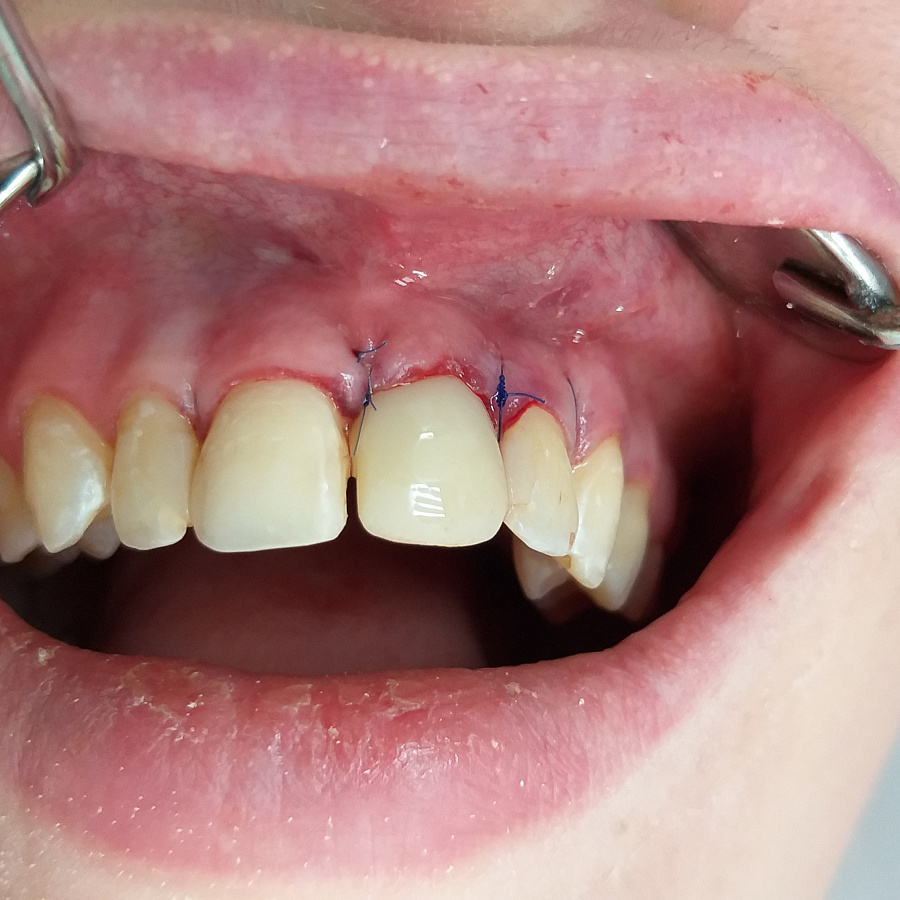

Следующий этап после удаления разрушенного корня и установки зубного имплантата - восстановление косметического дефекта временной коронкой, изготовленной после операции.

Результат лечения